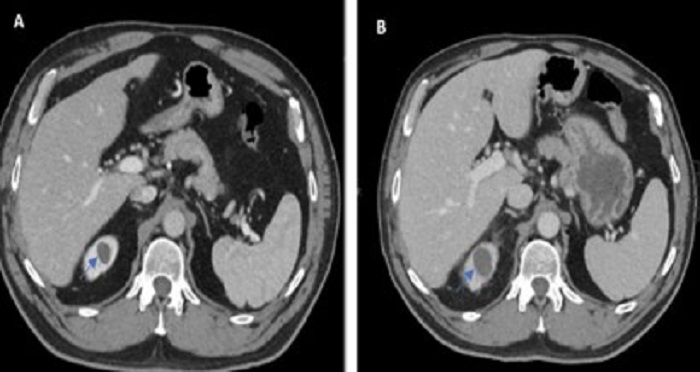

(Sumber foto: Mansour et al., 2023)

Hasil pemeriksaan CT-Scan pada pasien tersebut menunjukkan perubahan ginjal kanan karena kista. Gambar A menunjukkan kista berukuran 18 mm (pemeriksaan tiga tahun yang lalu). Sedangkan gambar B menunjukkan penumpukan lemak perinefrik, perubahan ukuran kista dari 18 mm ke 26 mm, dan peningkatan densitas kista dari 12,8 HU menjadi 22 HU.